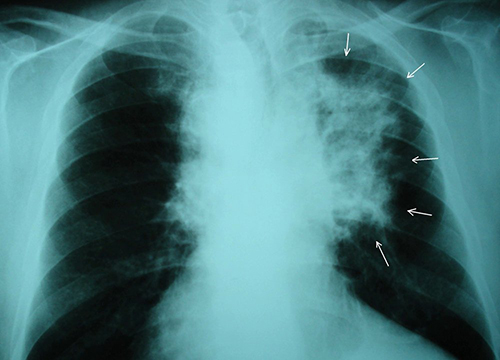

Ученые из Калифорнийского университета в Сан-Диего разработали новый метод лечения, который может предотвращать метастазирование рака в легкие. В основе разработке вирус, который поражает растение черноглазый горох.

При проверке нового подхода на мышах, инженеры обнаружили, что лечение не только замедлило рост опухоли в легких животных с метастатическим раком груди или меланомой, но также предотвратило или резко минимизировало распространение этих видов рака в легкие здоровых мышей, которые были заражены намеренно. Работа была представлена в журнале Advanced Science.

Лечение включает в себя инъекцию вируса мозаики коровьего гороха. Он безвреден для людей и животных, но организм регистрирует его как нечто чужеродное, что провоцирует иммунный ответ. В основе идеи – использование растительного вируса для обучения иммунитета на распознавание и уничтожение раковых клеток в легких.